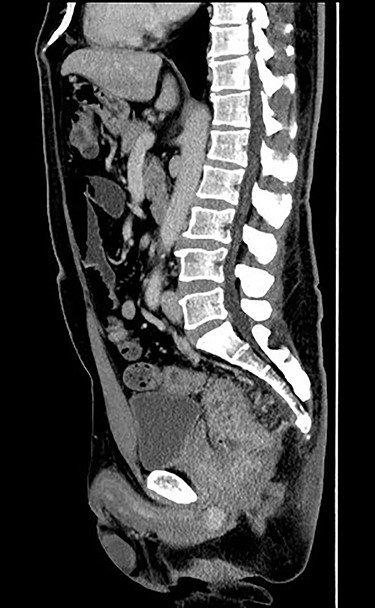

Case 1 was a 44-year-old man with a BMI of 26.9 kg/m [2], who was diagnosed as having lower rectal cancer with regional lymph node metastasis and direct prostate invasion (T4b, N1, M0 stage IIIc) (Fig. 1). The patient underwent preoperative chemotherapy followed by surgery. We docked da Vinci Xi from the lower left of the patient. The camera port was in the umbilical region, and the left 8 mm port was placed somewhat caudal from the placement of the port for rectal surgery, considering the operation procedure in urology. The surgical procedure involved dissection of the lymph node and blood vessel knot separation according to the normal procedure. Regarding rectal detachment, the posterior and lateral walls of the rectum were exfoliated as passively as possible (Fig. 2a), and the anterior wall was also exfoliated passively to the seminal vesicle position. After removal of the rectum, the oral intestinal tract was dissected with the sigmoid colon. Thereafter, dissection of the bilateral lymph nodes was performed (Fig. 2b), and the operation was transferred to urology. At that time, retargeting was set to the pelvic midline. In the urology department, resection of the prostate was performed (Fig. 2c–e), and a specimen was removed from the perineum. Subsequently, a colostomy was created and the operation was completed. The operation time was 949 min and the blood loss was 290 ml. The tumor was extending almost all around and directly invaded the prostate (Fig. 3). Pathologically, poorly differentiated adenocarcinoma including signet ring cell carcinoma was the main subject. The effect of chemotherapy was grade 0, and no effect was obtained by chemotherapy.

Enhanced computed tomography (CT) scan (sagittal image). Enhanced CT scan showed that the rectal tumor directly invades the prostate.